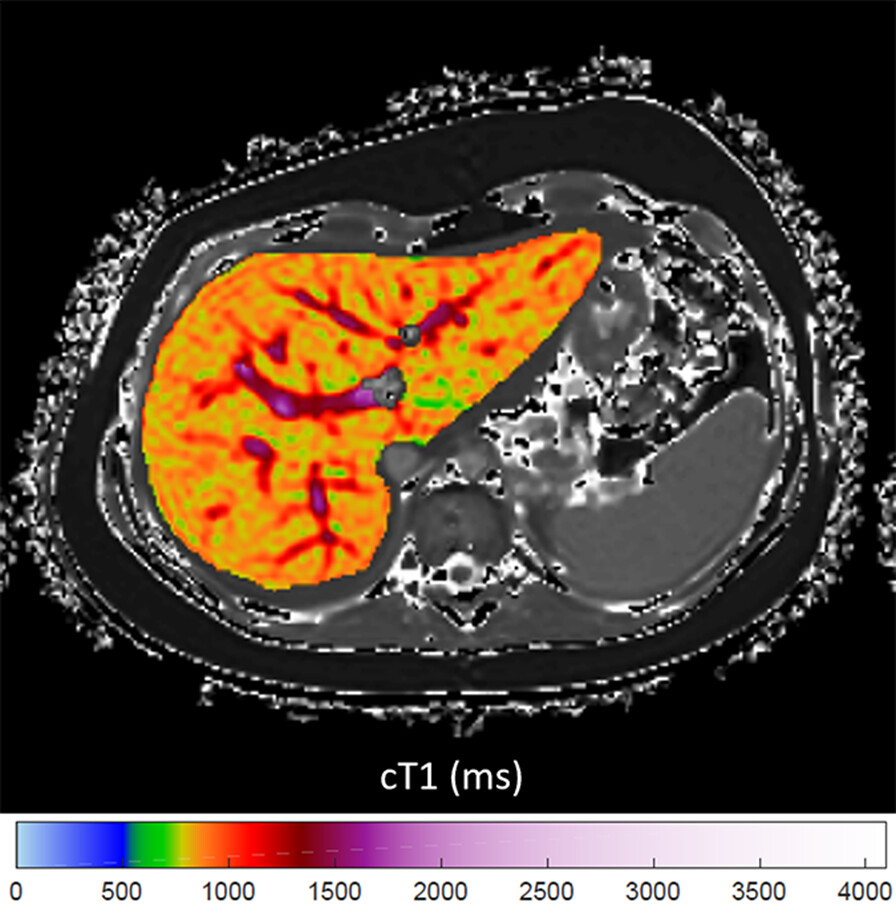

This review describes the acquisition, postprocessing, and analysis of T1 maps in the abdomen and explores applications in the liver, spleen, pancreas, and kidney. ajronline.org/doi/10.2214/AJ…

This review describes the acquisition, postprocessing, and analysis of T1 maps in the abdomen and explores applications in the liver, spleen, pancreas, and kidney.

ajronline.org/doi/10.2214/AJ…